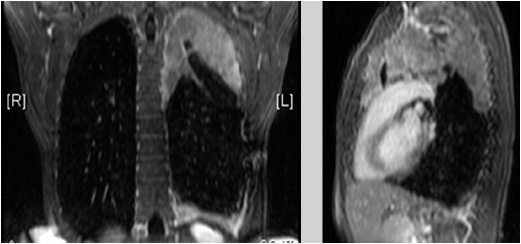

In fact, most people don't even know what it does. Malignant Mesothelioma | Oncohema Key

Malignant Mesothelioma | Oncohema Key from oncohemakey.com